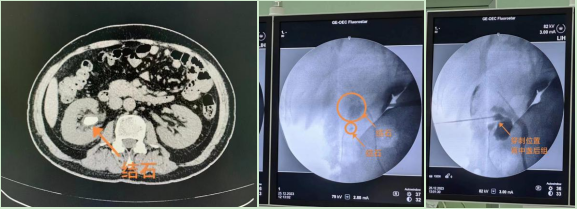

近日,我院泌尿外科由佘冰副主任医师主刀成功完成首例超声联合X线定位经皮肾镜碎石取石术。患者男性,61岁,因“右侧腰背部隐痛4年”就诊。CT报:双肾结石,右侧肾盂及输尿管积水、扩张。温宇红副主任主持术前讨论指示:患者右肾多发结石,直径较大者2.4cm,右肾下盏多发小结石,输尿管软镜手术需分次手术,费用较高,治疗周期长。经皮肾镜手术可一期治疗,清石率高,可行经皮肾镜取石术。

患者麻醉成功后在超声及X线引导下在十一肋间腋后线处穿刺,穿刺针进入右肾中盏,拔除针芯后注入造影剂,观察穿刺部位为肾盏穹窿处,沿穿刺针置入导丝,逐级扩张通道,置入输尿管镜,观察肾盂可见2.5cm大小黄褐色结石,下盏有直径1.0cm结石,钬激光击碎结石,冲出结石碎块,找到肾盂输尿管接口,置入导丝,沿导丝置入输尿管支架管,X线摄片观察输尿管支架位置正确,置入肾造瘘管并固定,手术顺利完成。